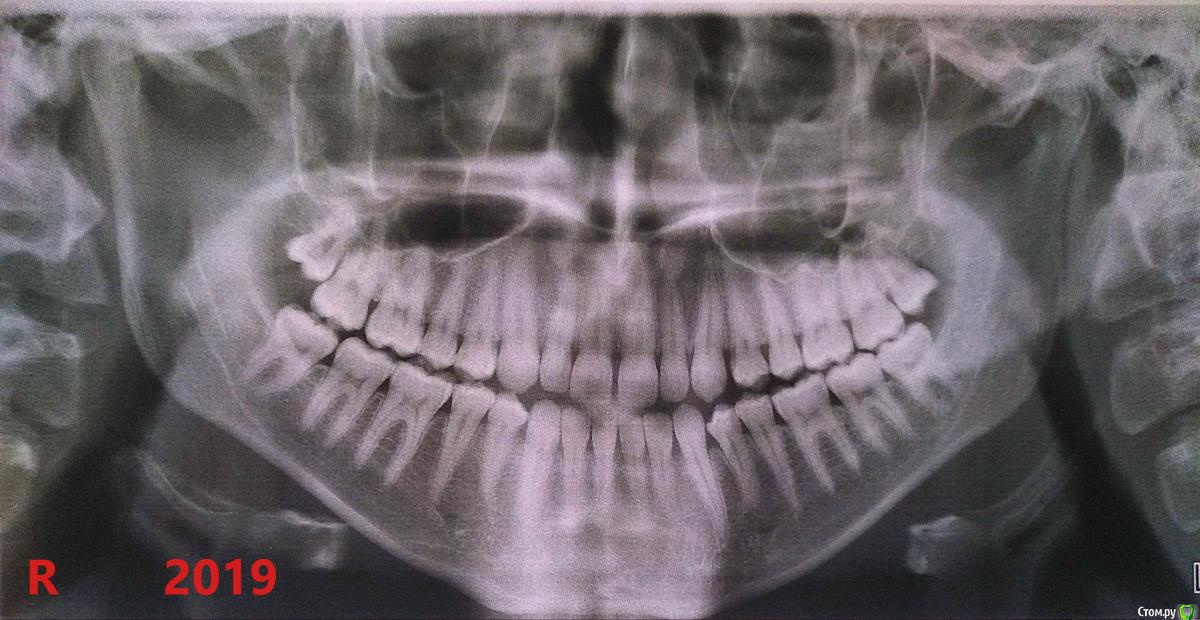

volosyslav.tkacuk Опубликовано 4 августа, 2019 Поделиться Опубликовано 4 августа, 2019 Доброго времени суток. Имею вот такую ситуацию, которую рекомендовали врачи исправить еще в 10-13 лет, но мама отказывалась... Так же, помню предлагали подрезать уздечку - мама отказалась, пока был под её опекой, тема ортодонтии и стоматологии заканчивалась словами «Занимайся спортом, подтягивайся, и зубы станут нормальные!», и не только. В июле наконец-то выбрал ортодонта из трёх, двое из которых предлагали одинаковые способы лечения — выбрал того, кто понравился по поведению. Зубы стираются, жевать сложно часто, зажевываю щёку-язык, сустав щёлкает и болит более 5ти лет, волнообразное открывание челюсти с уходом в сторону блльного сустава (влево). В закрытом состоянии тоже немного есть ассиметрия расположения челюсти. План лечения сделали такой: 1. Одновременная установка б/с на обе челюсти + положили накладки на нижние шестёрки.2. Через 4-5 месяцев установка CS системы от DynaFlex, для задвижения нижней челюсти назад. При первичной консультации врач сказала, что это «исключительно хирургический случай», но после попросила снимки суставов и увидев их, выдала именно такой план лечения как сверху. Прошу совета, правильный ли метод лечения выбран? Не станет ли больше проблем с суставом? Не вгонят ли его в компрессию? Поможет ли исправление смыкания в ситуации с ВНЧС? По заверениям врача — место, куда задвигать сустав есть, и что то положение в котором он есть сейчас — не его "родное", а последствия генетики и зубов, смыкание которых и вывело сустав вперёд. Врачу доверяю, но тревога присутствует. PS. ПОДПИСИ НА СНИМКЕ СУСТАВОВ ПЕРЕПУТАНЫ. ПО КРАЯМ — ЗАКРЫТОЕ СОСТОЯНИЕ, ПО СЕРЕДИНЕ — ОТКРЫТОЕ. Заранее Всем спасибо. Ссылка на комментарий